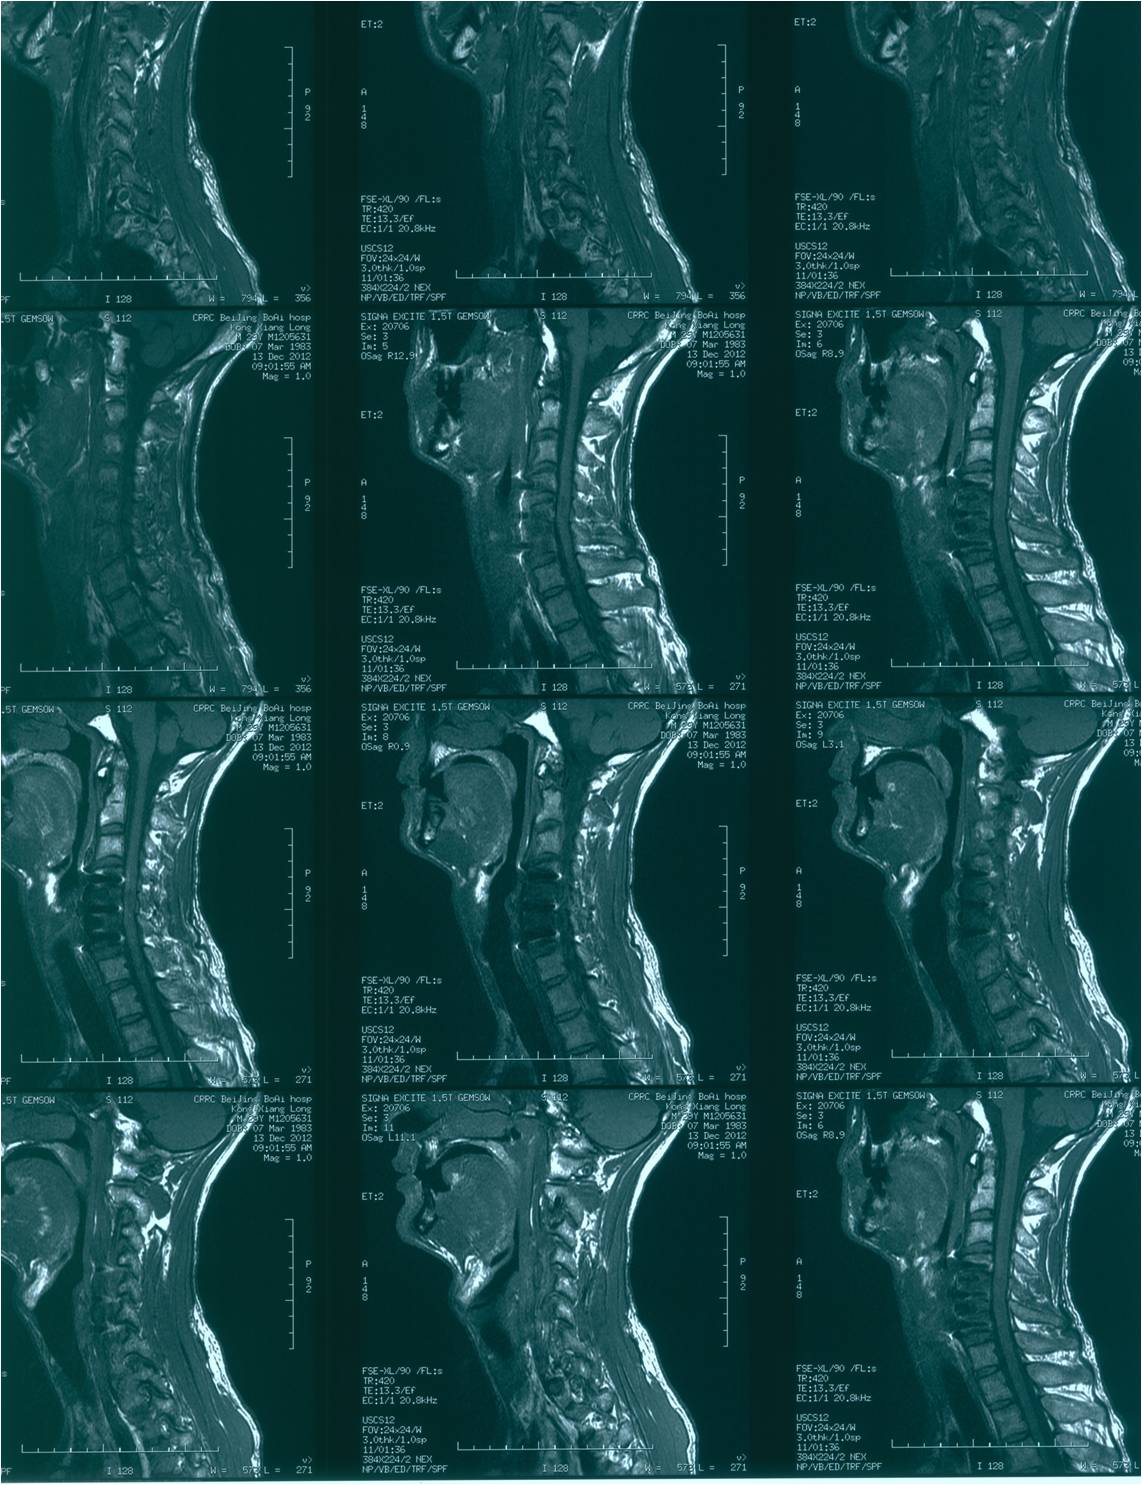

2012-11-18 车祸致四肢感觉、运动及二便功能障碍。

查体:意识清楚,呼吸均匀,查体合作。双侧感觉平面颈4,运动平面颈5. 颈6以下轻触觉保留至肛周,针刺觉消失。颈5以下只有肛门括约肌保留运动功能。下肢肌张力0级。腱反射消失。球海绵体反射可引出。当地医院行X片、CT、MRI检查